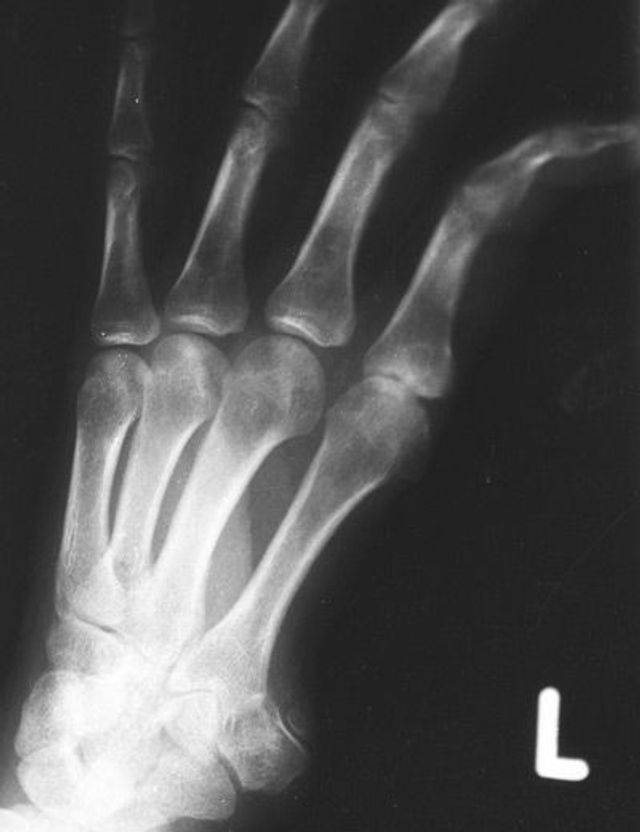

Dokumente des Grauens: Röntgenaufnahmen von Folteropfern

Hermann Vogel: Fotos von Folteropfern sind oft so brutal und direkt, dass der Betrachter reflexartig wegschaut. Anonyme Röntgenbilder sind besser auszuhalten. Zunächst erkennt der Betrachter nur, dass ein Finger fehlt oder ein Knochen zerbrochen ist. Das weckt sein Interesse und er will erfahren, was dem Menschen passiert ist. Die Bilder führen also dazu, dass sich die Menschen mit dem Thema Folter beschäftigen – auf erträgliche Weise. Und genau das ist mein Ziel.

Sie entlarven von außen nicht erkennbare Verletzungen, somit auch Spuren von Folter. Eine gerichtsmedizinische Untersuchung macht Frakturen, eingeführte Fremdkörper, Nadeln sichtbar. Die Aufnahmen ermöglichen eine Plausibilitätsprüfung. Stimmen die Schilderungen des Opfers mit dem Verletzungsmuster überein? Stimmt das Alter der Verletzung überein mit dem Zeitraum, den die Person für die erfahrene Folter angibt? Entspricht die Foltermethode dem, was für die angegebene Region und die verantwortliche Organisation, Militär oder Miliz, bekannt ist?